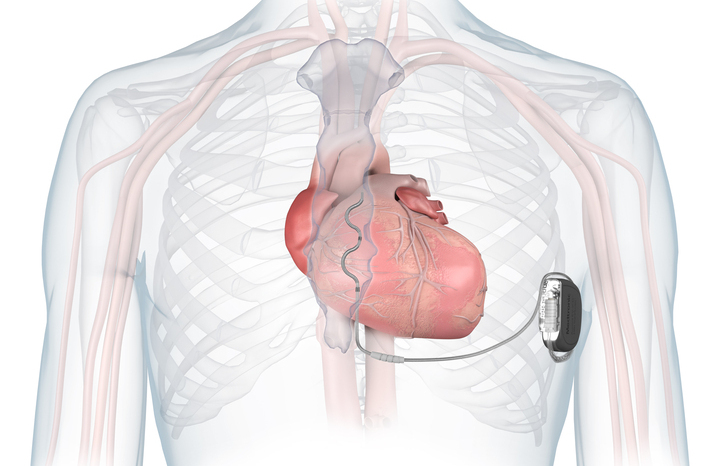

The algorithm-based technologies, HeartLogic and TriageHF, monitor readings from patients’ cardiac implantable electronic devices (CIEDs) such as pacemakers, so that clinicians can detect signs of potential deterioration earlier and intervene before hospital admission is needed.

Through Triage HF monitoring, patients have a simple transmitter box attached to their phoneline which automatically sends alerts from the patient’s pacemaker or implantable cardioverter-defibrillator to the heart failure team at the hospital if any dangerous, abnormal readings are identified.